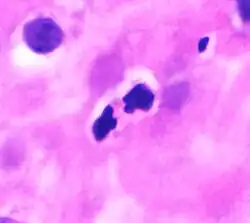

Eosinophil under the microscope (400×) from a peripheral blood smear. Red blood cells surround the eosinophil, two platelets at the top left corner.

In normal individuals, eosinophils make up about 1–3% of white blood cells, and are about 12–17 micrometres in size with bilobed nuclei.[3][5] While eosinophils are released into the bloodstream, they reside in tissue.[4] They are found in the medulla and the junction between the cortex and medulla of the thymus, and, in the lower gastrointestinal tract, ovaries, uterus, spleen, prostate, and lymph nodes, but not in the skin, lungs, esophagus, or some other internal organs under normal conditions. The presence of eosinophils in these latter organs is associated with disease. For instance, patients with eosinophilic asthma have high levels of eosinophils that lead to inflammation and tissue damage, making it more difficult for patients to breathe.[6][7] Eosinophils persist in the circulation for 8–12 hours, and can survive in tissue for an additional 8–12 days in the absence of stimulation.[8] Pioneering work in the 1980s elucidated that eosinophils were unique granulocytes, having the capacity to survive for extended periods of time after their maturation as demonstrated by ex-vivo culture experiments.[9]